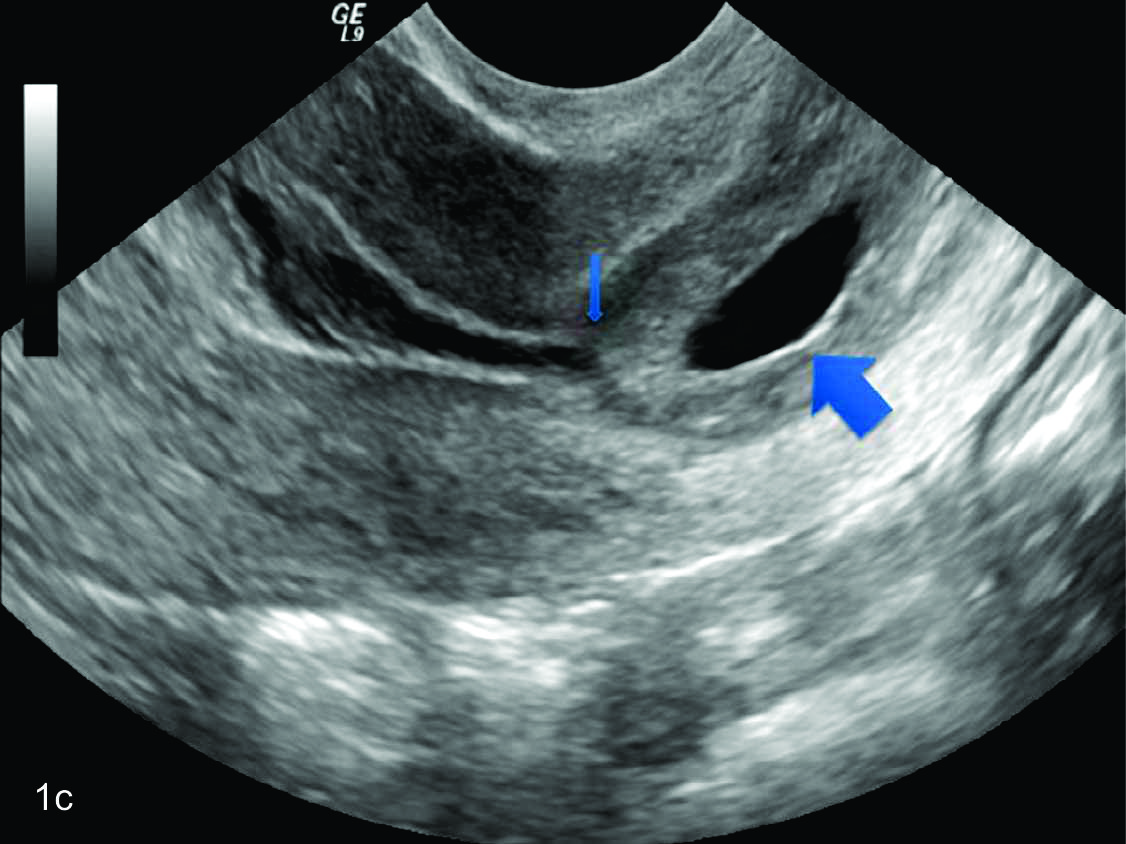

El uso generalizado de la ecografía transvaginal en la valoración de la gestación precoz en el primer trimestre del embarazo ha facilitado la detección de embarazo ectópico cervical. El diagnóstico preciso de la patología requiere que el ecografista esté familiarizado con las distinciones entre el embarazo cervical, aborto cervical y embarazo intrauterino en su estadio precoz. Se han propuesto criterios diagnósticos estrictos, debiendo estar la placenta y todo el saco coriónico que contiene el embarazo en vivo por debajo del orificio interno y el canal cervical debe estar dilatado. (2) En el embarazo ectópico cervical el orificio cervical interno se encuentra completamente cerrado. (figuras 1 y 2)

Figura 1

1a) Útero en plano sagital,

donde se evidencia el endometrio, el orificio cervical interno cerrado, destacando la presencia de imagen quística a nivel del cuello uterino (flecha). 1b) y d)Se observa el saco gestacional a nivel cervical con embrión en su interior.

Figura 2

Ecografía trans vaginal evidenciando útero en el plano sagital.

Se observa saco gestacional a nivel cervical (flecha gruesa), y orificio cervical interno cerrado (flecha fina). El endometrio está engrosado.